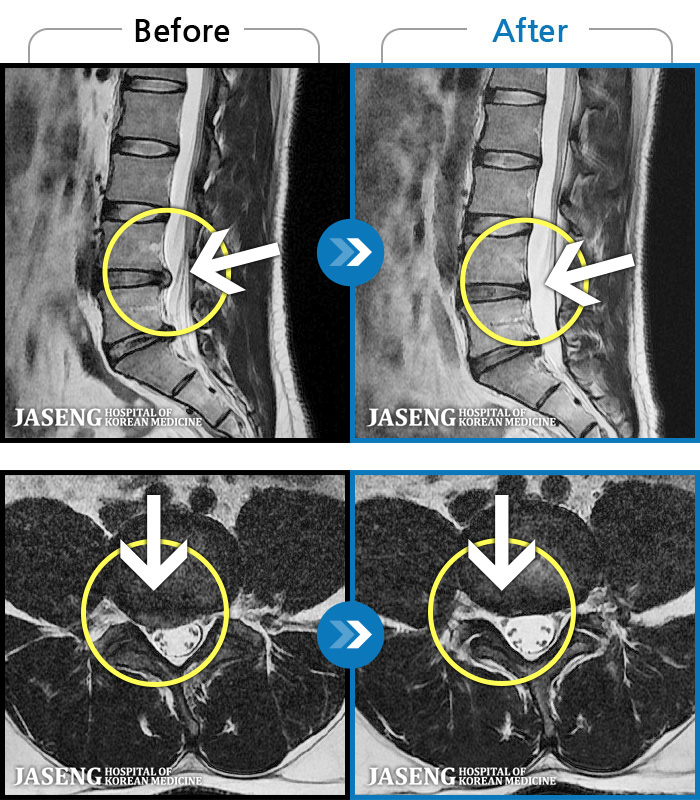

1,268 MRI ũ ʸ Ȯϼ.

ȯںп Ǹ ǿ ԿǾ, ο ġ ۿ Ƿ ġḦ Ͻñ ٶϴ.